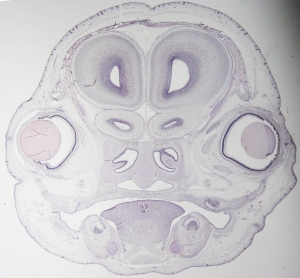

Stage 23

CfS 23

d41-44